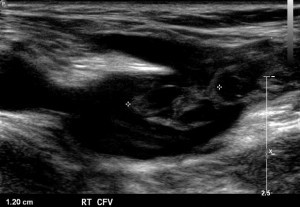

DVT and EHIT (Endovenous Heat-Induced Thrombosis) after EVLA

Deep vein thrombosis is rare in patients with EVLA. Approximately 0.5% to 1% of patients undergoing EVLA get a DVT. DVT can occur for numerous reasons. However, clot extending from the GSV into the CFV has been described. And there have been very rare reports of pulmonary embolism after EVLA. In a study of 2470 cases of radiofrequency ablation and 350 cases of EVLA 17 DVTs were found in the RFA group, 4 of which were EHIT (0.2%). In the EVLA group 4 DVTs were identified, 3 (0.9%) of which were EHIT. Whether EHIT has the same clinical significance and risk of pulmonary embolism is still unknown. Whether patients with EHIT should be anticoagulated, for how long, and with what type of anticoagulant, are still entirely unknown.

EHIT Classification: A classification system has been developed to help describe the locations of the thrombus after EVLA:

| Endovenous Heat-Induced Thrombosis (EHIT) classification | |

| EHIT level | Description |

| 1 | Closure with clot below the epigastric vein |

| 2 | Thrombus extending to the epigastric vein ostium |

| 3 | Thrombus extending to the sapheno-femoral junction |

| 4 | Thrombus bulging into the common femoral vein |

| 5 | Proximal thrombus extension adherent to the adjacent wall of the common femoral vein past the saphenofemoral junction |

| 6 | Proximal thrombus extension into the common femoral vein |

Once clot is adherent to the common femoral vein wall (Level 4 and above), anticoagulation is given. However, when thrombus is at the ostium of the GSV but not in the common femoral vein (Level 3) there is limited data and no real consensus. Some advocate for repeat duplex in 2-3 days to visualize whether there has been propagation of the thrombus.